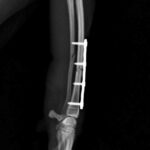

頻繁に嘔吐・下痢をするワンちゃんの精密検査依頼で内視鏡検査のご紹介がありました。内視鏡検査で上部・下部消化管を検査し、粘膜を採取し病理組織検査に出しました。結果は「胃:らせん菌感染を伴う慢性胃炎(中程度)/結腸:慢性腸炎(軽度)」とのことでした。その後かかりつけの先生のところ […]